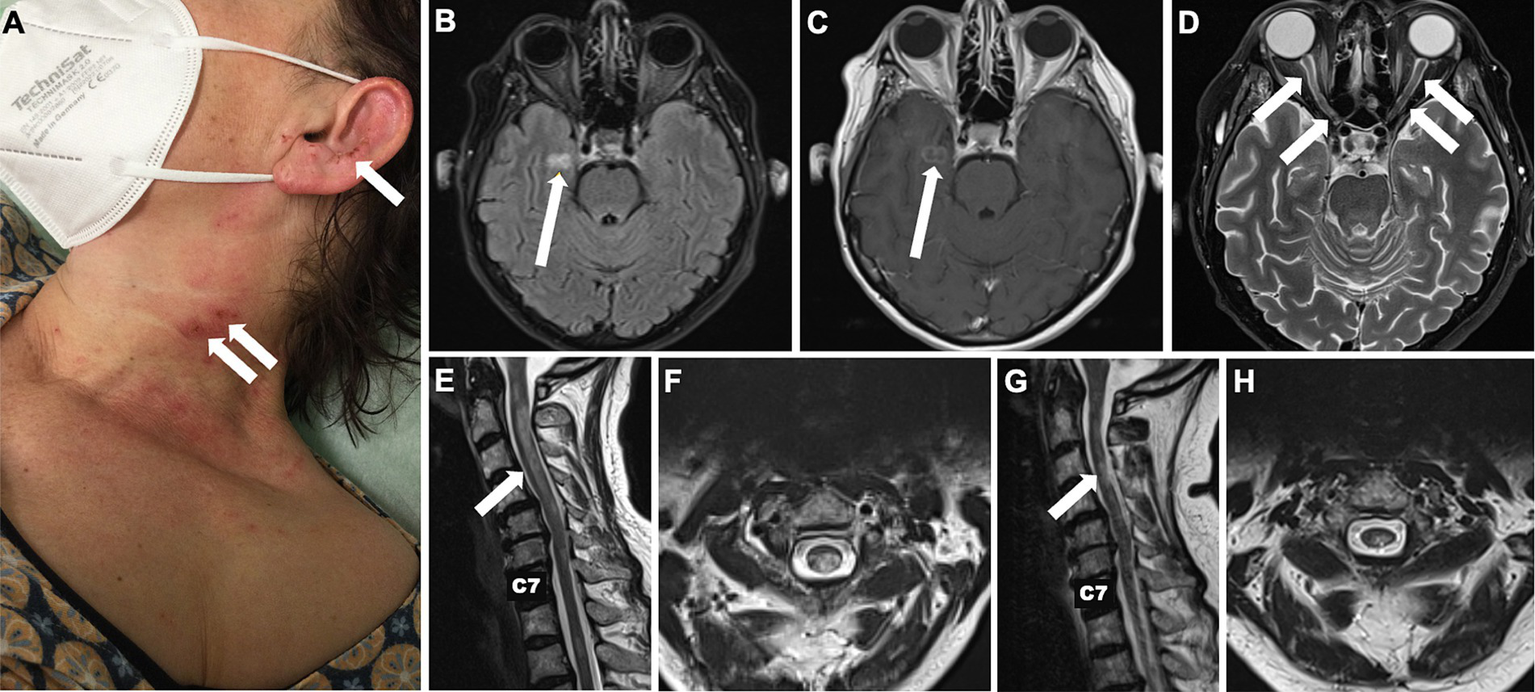

A 56-year-old female patient was initially admitted to a secondary care centre. Her medical history included arterial hypertension, type 2 diabetes mellitus and breast cancer undergone full remission following treatment more than 15 years ago. The patient had just returned from a pilgrimage when she noticed a subacute sensorimotor deficit in her left hand. Initially physicians suspected a stroke, but the brain magnetic resonance imaging (MRI) showed no signs of acute or subacute ischemia or inflammation. She was admitted for further diagnostic evaluation. The next day she complained of blurred vision with no reported loss of visual acuity at that time. Over the next 3 days there was a marked clinical deterioration: The patient developed a vesiculopapular rash with secondary clustered crustation on her neck, ear and décolletage (Figure 1A) and became increasingly agitated and confused. Cerebrospinal fluid (CSF) examination revealed a mild pleocytosis of 10 [0–4] /μl. Empirical antiviral treatment with aciclovir was started on suspicion of herpes zoster encephalitis. However, subsequent polymerase chain reaction testing of the CSF was negative for varicella-zoster, herpes simplex and other neurotropic viruses. A follow-up cerebral MRI revealed a right parahippocampal T2 lesion that was not evident on the initial MRI (Figures 1B,C). In addition, there were T2 hyperintense lesions in both optic nerves, which were consistent with optic neuritis (Figure 1D). At this point the patient was referred to our tertiary care facility.

Figure 1

Skin changes and longitudinal MRI of brain and spinal cord. Localised painful rash with crusts on the neck and lateral face initially due to repetitive scratching in central neuropathic pain syndrome initially misdiagnosed as herpes zoster reactivation (A). Cerebral T2-weighted FLAIR MRI showing a new hyperintense parahippocampal lesion that evolved within 6 days from symptom onset (B) and presented gadolinium enhancement (C). T2 hyperintense lesions in both optic nerves consistent with optic neuritis (D). Hyperintense spinal cord lesions compatible with cervical longitudinally extensive transverse myelitis reaching from the atlas to the 6th vertebra upon admission to our tertiary care centre (E,F) and after 6 months (G,H).

At a follow-up visit 3 months later, the patient reported being able to walk up to 500 m with a walker. The right eye remained blind, colour vision had returned to the left eye, but she was still unable to read a newspaper. A brain MRI showed a new inflammatory T2 lesion in the left frontal white matter, possibly representing paraclinical disease activity before the immunotherapy could take full effect. Prednisolone was reduced from 20 mg to 5 mg/d. When we administered the second cycle of INE at the six-month follow-up, there were no new cerebral lesions and the inflammatory cervical myelopathy decreased in volume (Figures 1G,H). Walking was unrestricted; unfortunately, the visual impairment remained unchanged. Clinical stability was maintained after 12 months of treatment. A synopsis of the clinical course is shown in Figure 2.